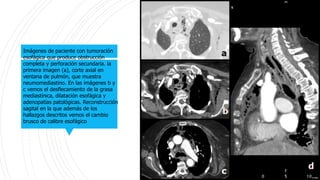

Imágenes de paciente con tumoración

esofágica que produce obstrucción

completa y perforación secundaria. la

primera imagen (a), corte axial en

ventana de pulmón, que muestra

neumomediastino. En las imágenes b y

c vemos el desflecamiento de la grasa

mediastínica, dilatación esofágica y

adenopatías patológicas. Reconstrucción

sagital en la que además de los

hallazgos descritos vemos el cambio

brusco de calibre esofágico